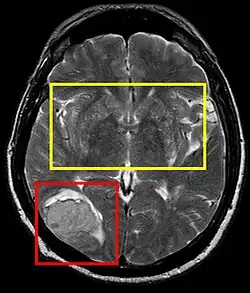

| Stroke brain (similar to cerebral softening) | |

Cerebral softening, also known as encephalomalacia, is a localized softening of the substance of the brain, due to bleeding or inflammation. Three varieties, distinguished by their color and representing different stages of the disease progress, are known respectively as red, yellow, and white softening.[1][2]